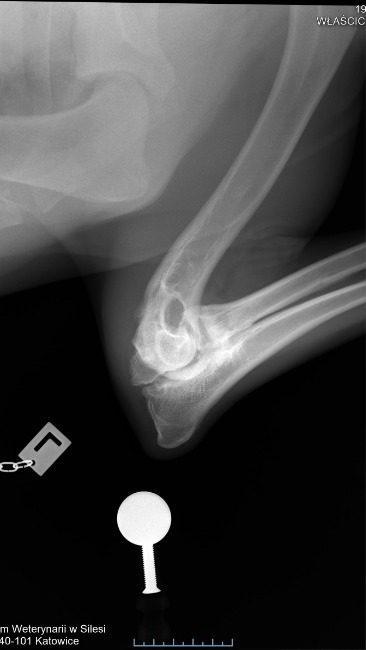

Późniejsze badanie RTG w katowickiej przychodni weterynaryjnej potwierdziło najgorsze obawy – stan łokci jest bardzo poważny, choć Axel nie wykazuje oznak bólu, co dziwi każdego specjalistę.

RTG + GT:

Łokcie – obustronnie, wyraźna inkongruencja, wyraźna podchrzęstna skleroza, cechy OA, UAP

Z weterynaryjnego na nasze: Cechy radiologiczne (Zmiany na RTG) pokazują:

OA - Artroza łokcia u psa to przewlekłe schorzenie zwyrodnieniowe stawu, prowadzące do bólu, sztywności i ograniczenia ruchu, spowodowane uszkodzeniem chrząstki i zmianami w kościach, często wynikające z dysplazji (np. niezrośnięty wyrostek dodatkowy - UAP)

• UAP: Ubytek kości podchrzęstnej w przyśrodkowej części bloczka kości ramiennej, czasem z wolnym fragmentem kostnym.

DIAGNOZA: ED – 3. Stopień

• ED (Elbow Dysplasia): Dysplazja stawu łokciowego, wada rozwojowa, która powoduje zaburzenia w budowie i funkcjonowaniu stawu.

• 3. stopień (ED 3/3): Określa najcięższą formę tej dysplazji, czyli ciężką dysplazję.